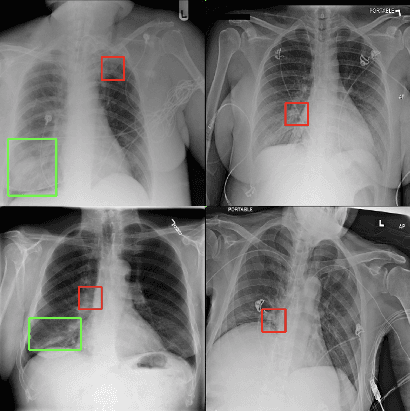

Abstract:Saliency maps have become a widely used method to make deep learning models more interpretable by providing post-hoc explanations of classifiers through identification of the most pertinent areas of the input medical image. They are increasingly being used in medical imaging to provide clinically plausible explanations for the decisions the neural network makes. However, the utility and robustness of these visualization maps has not yet been rigorously examined in the context of medical imaging. We posit that trustworthiness in this context requires 1) localization utility, 2) sensitivity to model weight randomization, 3) repeatability, and 4) reproducibility. Using the localization information available in two large public radiology datasets, we quantify the performance of eight commonly used saliency map approaches for the above criteria using area under the precision-recall curves (AUPRC) and structural similarity index (SSIM), comparing their performance to various baseline measures. Using our framework to quantify the trustworthiness of saliency maps, we show that all eight saliency map techniques fail at least one of the criteria and are, in most cases, less trustworthy when compared to the baselines. We suggest that their usage in the high-risk domain of medical imaging warrants additional scrutiny and recommend that detection or segmentation models be used if localization is the desired output of the network. Additionally, to promote reproducibility of our findings, we provide the code we used for all tests performed in this work at this link: https://github.com/QTIM-Lab/Assessing-Saliency-Maps.

Abstract:Saliency maps have become a widely used method to assess which areas of the input image are most pertinent to the prediction of a trained neural network. However, in the context of medical imaging, there is no study to our knowledge that has examined the efficacy of these techniques and quantified them using overlap with ground truth bounding boxes. In this work, we explored the credibility of the various existing saliency map methods on the RSNA Pneumonia dataset. We found that GradCAM was the most sensitive to model parameter and label randomization, and was highly agnostic to model architecture.